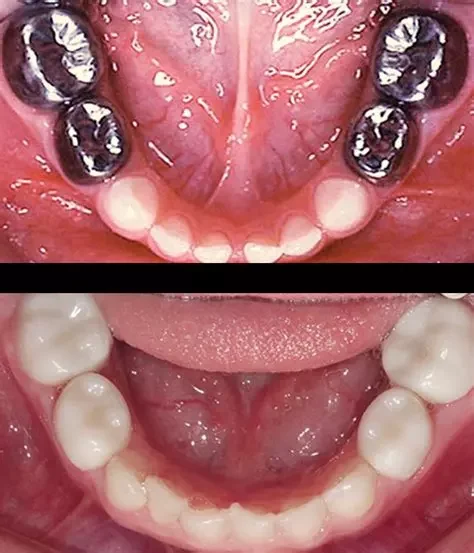

Odontologia Pediatrica

La ortodoncia pediátrica detecta y corrige a tiempo problemas de desarrollo dental en niños, guiando el correcto crecimiento de los maxilares.

Coronitas Niños

Las coronas infantiles protegen y restauran dientes temporales muy dañados, manteniendo su función y estética hasta su recambio natural.